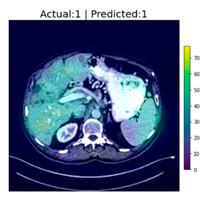

After reaching an accuracy of 95.89%, the training was stopped, and the Grad-CAM method was applied for each of the test images, including those that were falsely classified. The following figure, Figure 6, shows some of the CT images with their associated heat-maps overlaid. In the legends of the figures, “Actual” shows the label for DeepLesion, and “Predicted” shows the output of the CNN classifier.

Figure 6.

CT images with Grad-CAM-generated heat-maps overlaid.